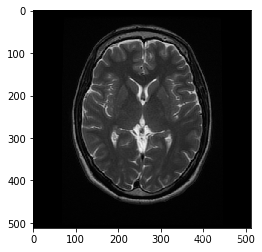

# 读入图像

image = cv2.imread('images/brain_MR.jpg')

# 制作图像副本

image_copy = np.copy(image)

# 将颜色更改为RGB(从BGR)

image_copy = cv2.cvtColor(image_copy, cv2.COLOR_BGR2RGB)

plt.imshow(image_copy)

<matplotlib.image.AxesImage at 0x7f9b454dae48>